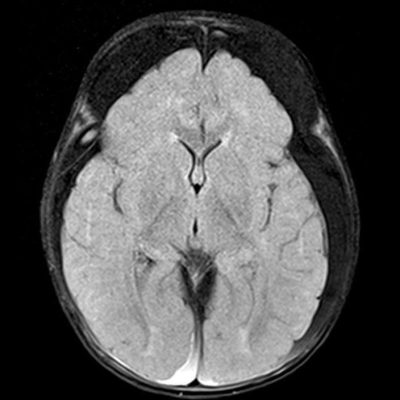

- A) Bilateral serebral konveksitede subdural higroma

- E) Subdural hematohigroma ile uyumlu yoğun içerikli bileşenler

- Subdural hematom: En sık görülen radyolojik bulgudur, vakaların %83-90’ında saptanır. Genellikle bilateraldir ve farklı yaşlarda hemorajik elemanlar içerir.

- Subdural higroma: Araknoid yırtıklara bağlı gelişir. Köprü ven yaralanması ile birlikte olduğunda hemorajik bileşenler içerebilir (hematohigroma).

- Köprü ven trombozu: Manyetik duyarlılık görüntülemede, kortikal ven trasesinde duyarlılık artefaktı olarak ya da “lolipop” ve “iribaş” (tadpole) işareti şeklinde görülür. Vakaların yaklaşık %30-45’inde saptanır.